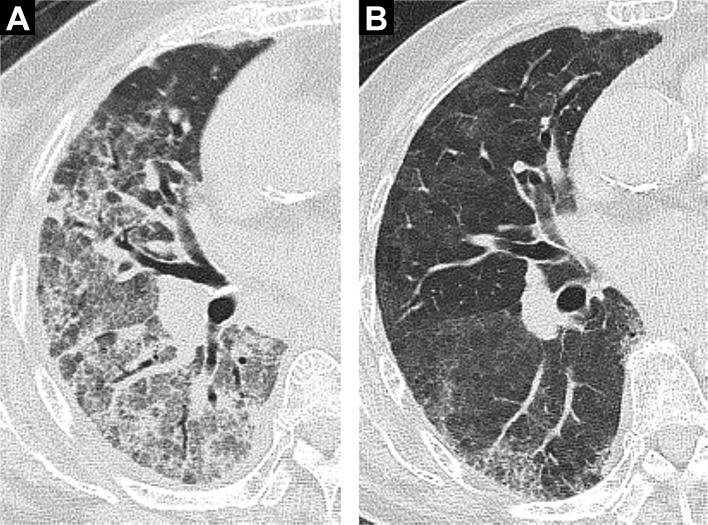

The Acute Physiology and Chronic Health Evaluation II scores were significantly lower in the drug-associated ARDS group than in the non-drug-associated ARDS group (median (IQR): 18.0 (16.5-21.0) vs 23.0 (18.0-26.0), p<0.001), and the arterial oxygen tension/fractional inspired oxygen ratio was higher (148.0 (114.1-177.5) vs 101.0 (71.5-134.0), p=0.003). In the drug-associated ARDS group, although high-resolution CT scores indicative of the extent of fibroproliferation (301.6 (244.1-339.8) vs 208.3 (183.4-271.6), p<0.001), serum lactate dehydrogenase levels (477 (365-585) vs 322 (246-434), p=0.003) and the McCabe scores (score 1/2/3, n (%): 20 (74)/4 (15)/3 (11)vs154 (91)/7 (4)/9 (5), p=0.04) were significantly higher, ventilator weaning was earlier (p<0.001) and 28-day mortality was better (p=0.043). After adjusting for potentially confounding covariates, drug-associated ARDS group was associated with lower 28-day mortality (adjusted HR (HR) 0.275; 95% CI 0.106 to 0.711; p=0.008).

药物相关性 ARDS 组的急性生理学和慢性健康评估 II 评分明显低于非药物相关性 ARDS 组(中位数(IQR):18.0(16.5-21.0)比 23.0(18.0-26.0),p<0.001),动脉血氧分压/吸入氧分数比更高(148.0(114.1-177.5)比 101.0(71.5-134.0),p=0.003)。在药物相关性 ARDS 组中,尽管提示纤维增生程度的高分辨率 CT 评分较高(301.6(244.1-339.8)比 208.3(183.4-271.6),p<0.001)、血清乳酸脱氢酶水平(477(365-585)比 322(246-434),p=0.003)和 McCabe 评分(评分 1/2/3,n(%):20(74)/4(15)/3(11)比 154(91)/7(4)/9(5),p=0.04)较高,但呼吸机撤机更早(p<0.001),28 天死亡率更好(p=0.043)。在调整了潜在混杂因素后,药物相关性 ARDS 组与较低的 28 天死亡率相关(调整后的 HR(HR)0.275;95%CI 0.106 至 0.711;p=0.008)。